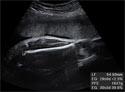

Ecografía: Medición del perímetro abdominal

Es el contorno por encima del ombligo fetal

Ecografía de la medición del perímetro del abdomen fetal en el tercer trimestre de embarazo

Corresponde al contorno del abdomen fetal ligeramente por encima del ombligo. En esta imagen podemos ver con claridad ese perímetro, enmarcado en el círculo blanco.